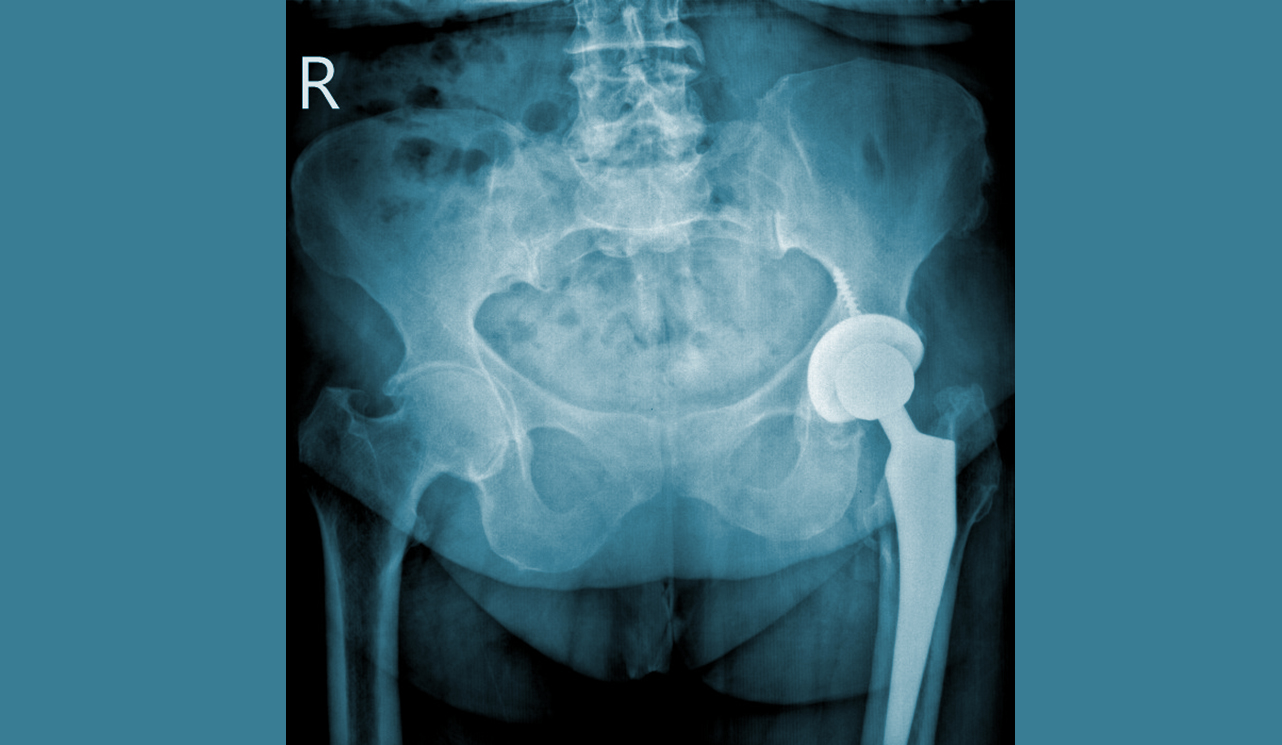

Kalça eklemi kireçlenmelerini temel olarak ikiye ayırabiliriz. Daha sık karşılaştığımız birinci grupta doğumsal yada sonradan oluşan yapısal bir bozukluk (kalça çıkığı, artrit, travma vb) nedeniyle zaman içinde kalça eklemindeki kıkırdakların aşınması sonucu ortaya çıkan kireçlenmeler yer alırken, ikinci grupta idiyopatik olarak adlandırdığımız sebebi belirlenemeyen kalça kireçlenmeleri yer alır.

Kalça eklemi kireçlenmesi, genelde 60 yaşından sonra görülse de özellikle doğumsal kalça çıkığı ve çocukluk çağında geçirilen kalça eklemi hastalıkları sonrasında çok erken yaşlarda da ortaya çıkabilir.